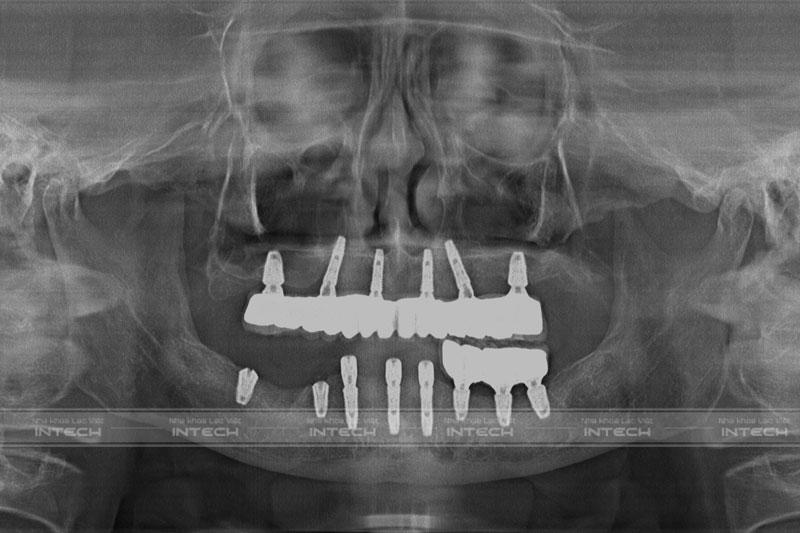

Hình ảnh phim chụp X-quang của chú Bảy sau khi trồng răng ImplantHình ảnh phim chụp X-quang của chú Bảy sau khi trồng răng Implant

Quá trình trồng răng Implant của chú Bảy diễn ra theo đúng với kế hoạch điều trị ban đầu của bác sĩ. Cảm nhận về quá trình trồng răng Implant tại Lạc Việt Intech, chú Bảy cho biết:

“Chú cảm thấy mình cũng hơi liều, cấy 9 trụ Implant trong vòng 2 tiếng. Ban đầu cũng sợ lắm thế nhưng trải nghiệm xong mới thấy thực sự là không đau tí nào cả. Sau khi hết thuốc tê chú cũng không cảm thấy khó chịu lắm, uống thuốc giảm đau là hoàn toàn bình thường. Sau khi cấy ghép Implant xong, bác sĩ có làm cho chú hàm tạm để đảm bảo thẩm mỹ, giúp chú có thể thoải mái giao tiếp và ăn nhai”.

• Trồng răng Implant All On 6 toàn 2 hàm.